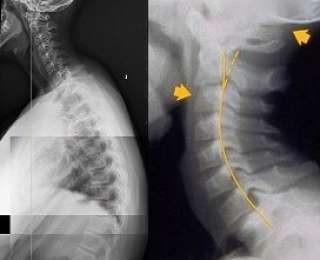

Эти шокирующие рентгеновские снимки показывают подростков и детей, у которых растут горбы и изгибается шея из-за пристрастия к смартфонам. Ведущий австралийский мануальный терапевт Джеймс Картер предупредил, что состояние «текстовая шея» вызывается характерным наклоном шеи над телефонами и планшетами в течение нескольких часов и становится эпидемией.

Доктор Джеймс Картер говорит, что 50 процентов таких людей составляют дети и подростки. Многие из них из-за этого страдают головными болями, болями в шее, плечах, спине и депрессивным состоянием.